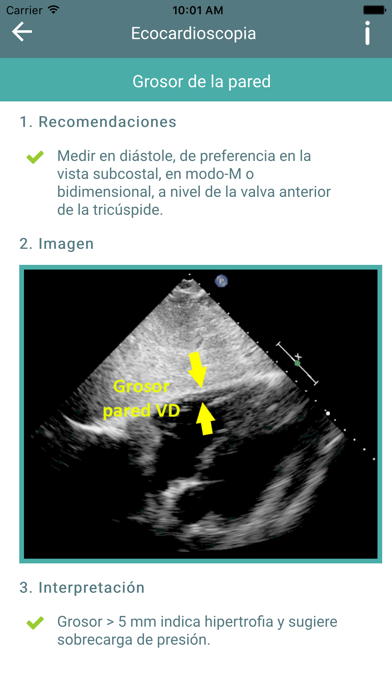

La aplicación de Ecocardioscopia que presentamos pretende ser una herramienta capaz de orientar al clínico que se enfrente a la sospecha de patología funcional o estructural del corazón, y facilitar el diagnóstico precoz, manejo, adecuada derivación y seguimiento de alteraciones cardíacas como la hipertrofia de ventrículo izquierdo, la insuficiencia cardíaca, valvulopatías, derrame pleural, etcétera.